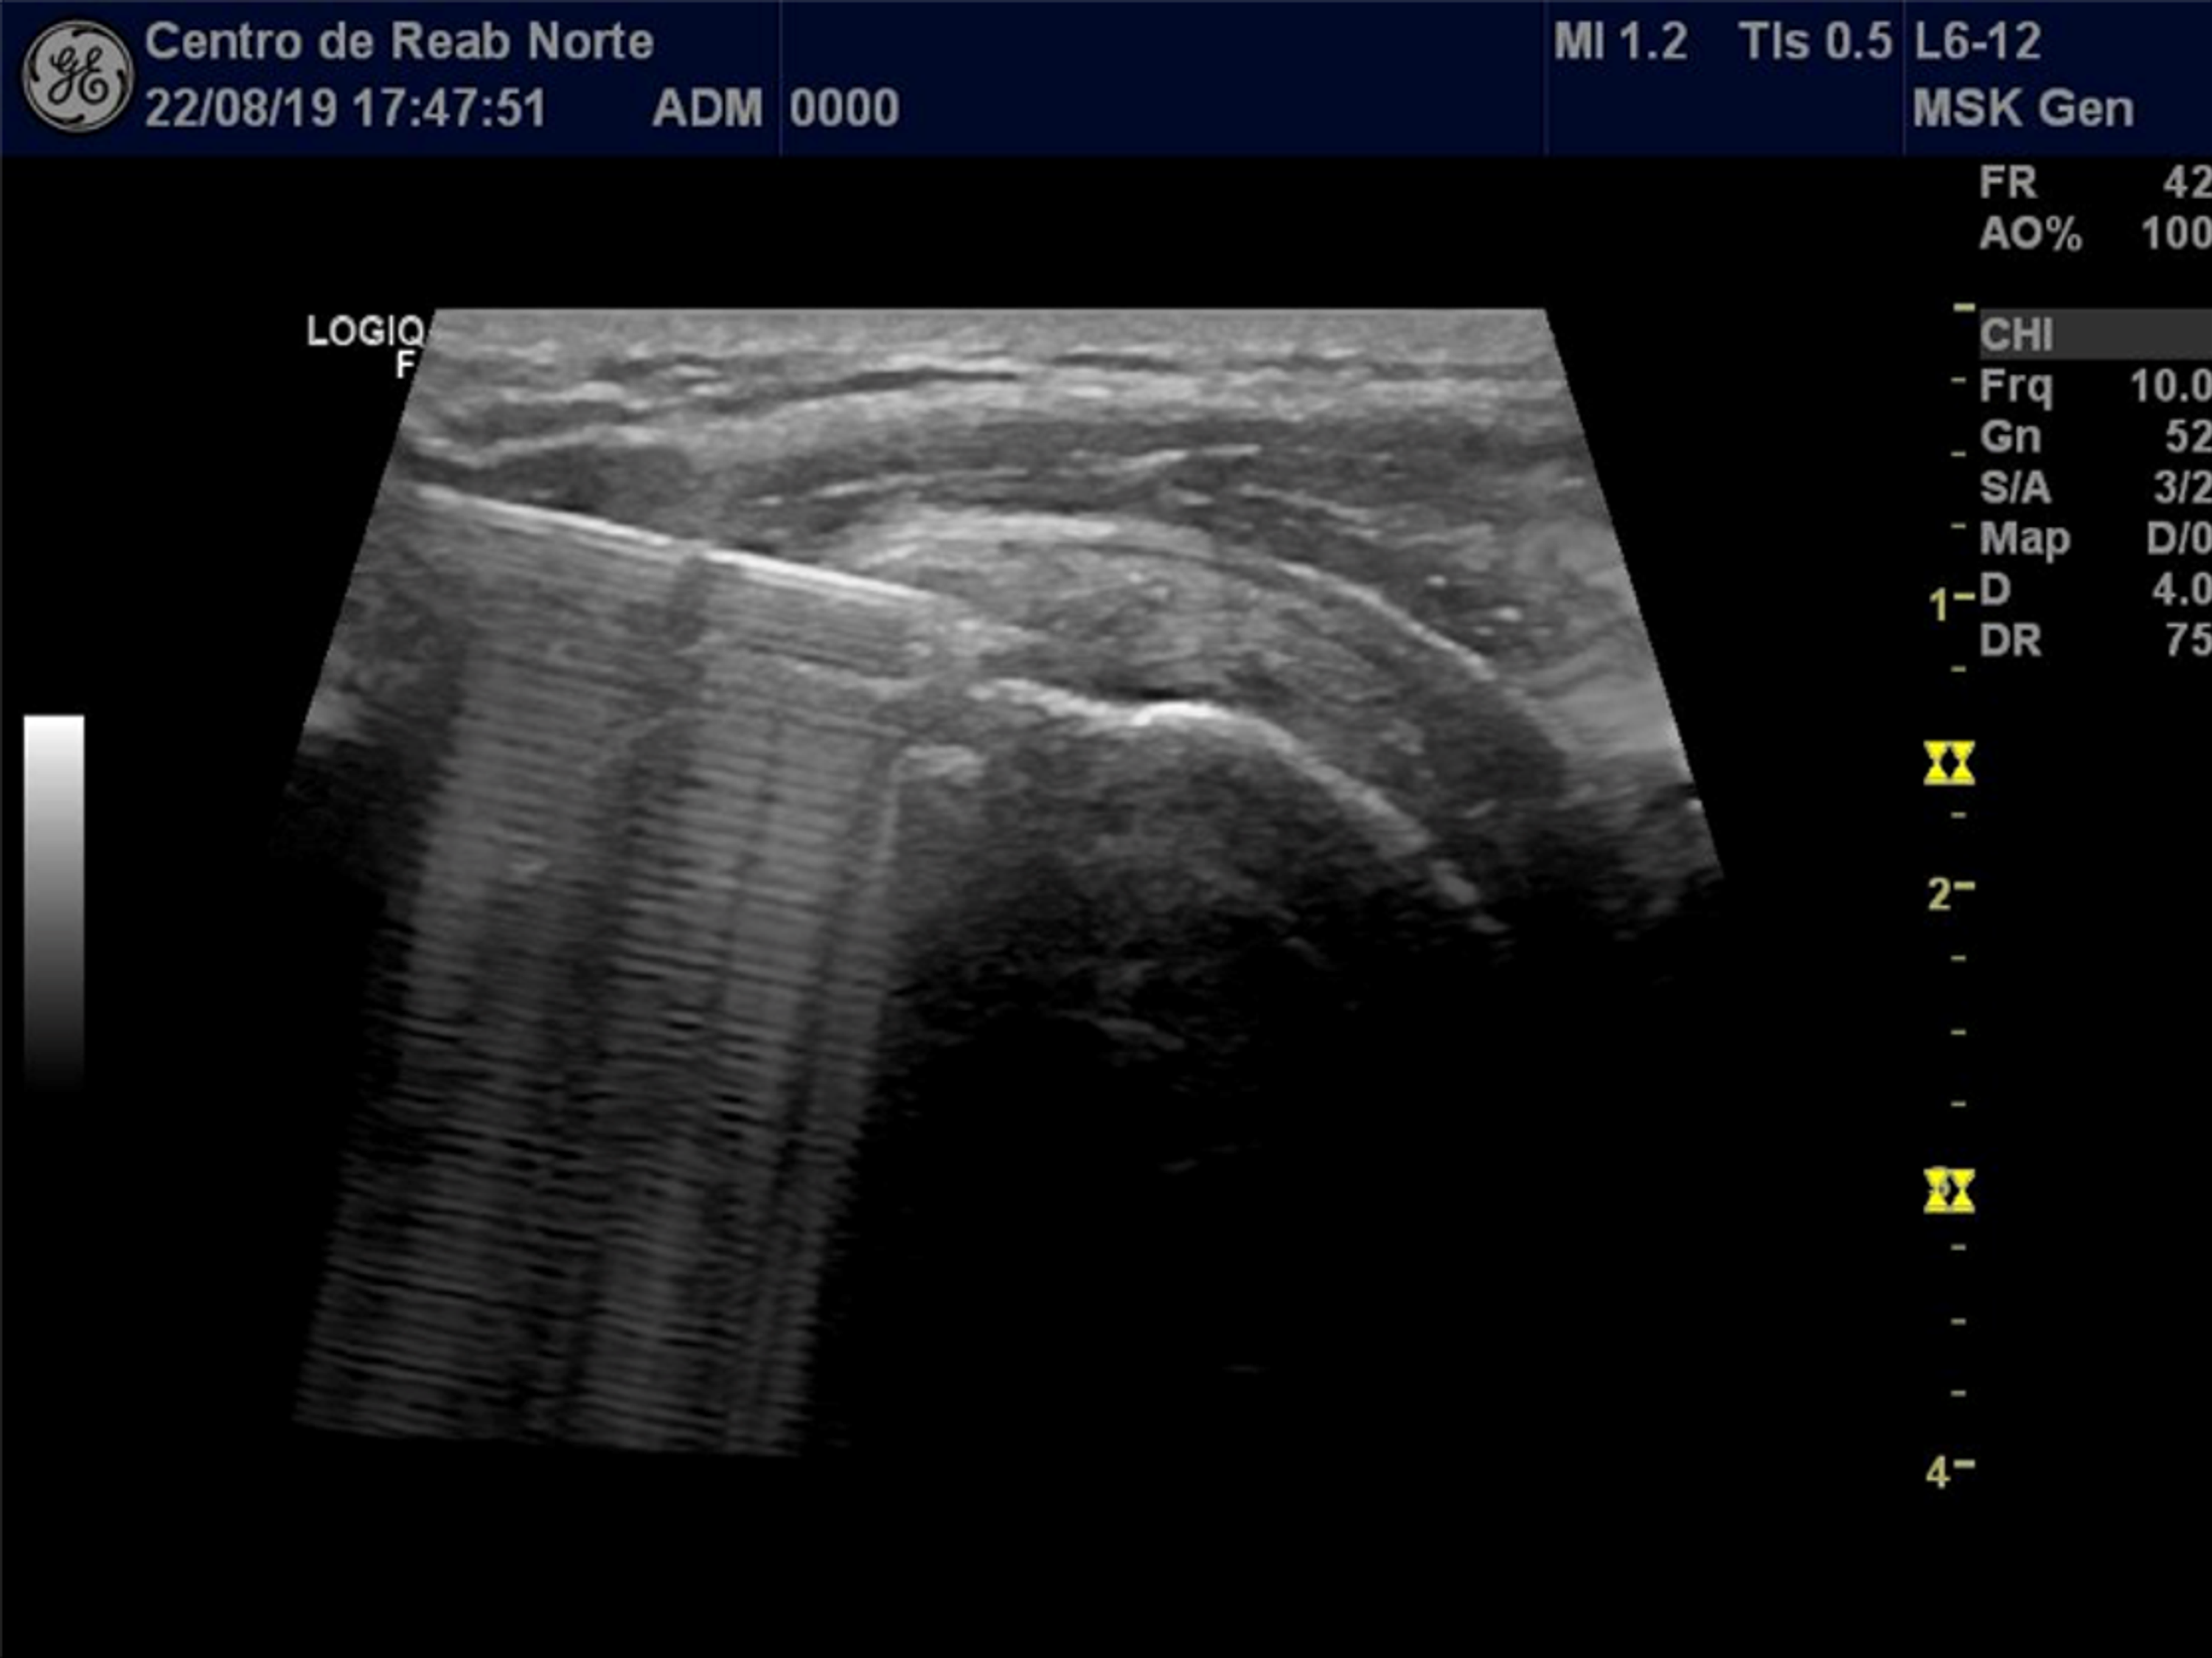

From www.mskultrasoundinjections.co.uk

Rotator cuff pain injection MSK US Injections Hyaluronic Acid Injection Rotator Cuff The present study demonstrated that pain and shoulder function were improved significantly after sh treatment. The use of ha in patients with rotator cuff tears improve vas and functional score in all trials that we have analyzed. A combined injection of hyaluronic acid and prp (weekly × 4 weeks) into the subacromial space was found to significantly. Hyaluronic Acid Injection Rotator Cuff.